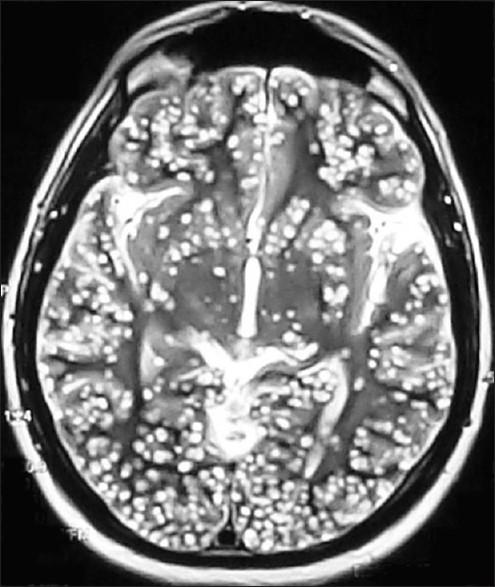

Neurocysticercosis (NCC), a common helminthic infestation in developing countries, may cause acquired epilepsy and neurological morbidities. Acute symptomatic seizure is the most common manifestation. The other clinical conditions include headache, hydrocephalus, chronic meningitis, focal neurological deficits, and psychological disorders. Altered sensorium and raised intracranial pressure (ICP) may require ventilatory support in an intensive care unit (ICU). Definitive diagnosis is made by identification of parasites in tissues or by a radiological demonstration of the scolex in cystic lesions. Antiepileptic drugs are used to control seizures after NCC. Steroids are generally administered along with antihelminthics, in order to control the edema and intracranial hypertension that may occur as a result of antiparasitic medications. In patients with intracranial hypertension, the priority is to manage the ICP before considering other treatment options. Antiparasitic drug treatment is never the mainstay of treatment, especially in the setting of elevated ICP. Here, we present the ICU management of two such cases.